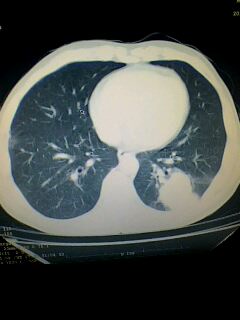

考虑左肺下叶周围型肺癌.图象欠清,请问病人贵更?

考虑左肺下叶周围型肺癌.

图像资料欠清,建议强化,考虑周围型肺癌。

左下肺肿块影,深分叶,考虑肺癌。

左下肺球形病灶,考虑:1:球形肺炎;2:周围型肺癌不除外,建议治疗后复查

不排除左肺下叶周围型肺癌可能!建议穿刺活检!

考虑左肺下叶周围型肺癌。

考虑左肺下叶周围型肺癌并阻塞性肺炎。

考虑左肺下叶周围型肺癌